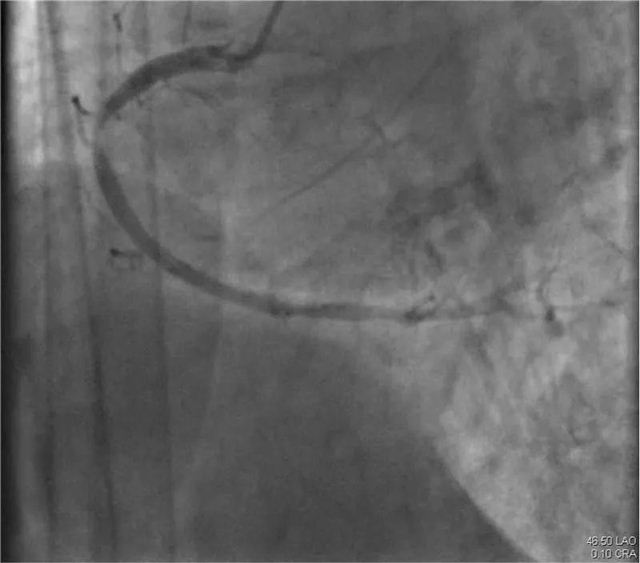

一面锦旗,不仅仅代表患者对疾病治疗效果的认可,更是对医护团队的认可。近日,年过八旬的逯奶奶和其家属将一面写有“精湛医术出妙手 体贴入微胜亲人”的锦旗送入长治市第二人民医院心血管内科医护人员手中,表达了患者对心血内科全体医护人员的感激之情。 患者家属说:“我母亲经过冯翠萍主任、王涛医生以及全体护理人员的积极治疗、精心护理,病情逐渐好转并康复出院。他们严谨、细心、热情的工作精神,精湛的医学技术,让我和我的家人非常感动和十分敬佩,非常感谢心血管内科全体医护人员,千言万语难表内心真情,唯有送上锦旗表示感谢。” 医术精湛 精心 患者逯奶奶已年过八旬,2023年11月发病至今的半年多时间里,多次因心肌梗死、心力衰竭,也多次就诊于我市多家医院;今年5月患者再次出现心绞痛症状,发作频繁,无法耐受,逯奶奶为求诊治就诊我院心血管内科进一步治疗。 入院后,主管医师王涛仔细询问病史并为其进一步进行检查。患者逯奶奶由于年岁已高,基础性疾病较多,既往曾在外院行冠脉造影术,血管扭曲,风险大。心血管内科主任冯翠萍、主管医师王涛再次为患者评估,患者为高龄,冠脉入路血管扭曲严重,手术风险极高;重新评估冠脉手术操作入路,因右桡动脉入路无法到达右冠,股动脉闭塞、狭窄无法进行穿刺,最终选择从左桡动脉进行手术。术中逯奶奶左侧动脉扭曲严重,在孙涛教授指导下,顺利找到罪犯血管,狭窄最重处达到99%,给予支架治疗,术后在心血内科医护人员的精心治疗和护理下,逯奶奶未再出现心绞痛发作,顺利康复出院。 冯翠萍主任亲切的说:“锦旗是赞许、是荣誉,更是对我们的鼓励和鞭策,一面锦旗承载着患者对医院的信任和感激,象征着医患情深,长治二院心血管内科团队将以此为动力,更加努力地为每一位患者提供更优质的诊疗方案及服务。” 病情分析 左侧动脉严重扭曲 右冠为罪犯血管,第一转折处节段性狭窄90-99% 右冠植入1枚支架术后,未见残余狭窄 科 长治市第二人民医院心血管内科成立于2011年1月,是长治市市级重点专科,是以临床药物治疗、心脏介入、心脏功能评估、心脏康复为主要手段,集临床、科研、教学、预防、康复为一体的综合性心血管专科。 心血管内科现有医护人员26人,其中硕士研究生4人、主任医师1人、副主任医师1人、主治医师6人、住院医师2人、副主任护师1人、主管护师3人、护师(士)8人。目前科室开放床位30张,重症监护病房(CCU)床位8张。科室能够诊治疾病有:冠心病、各种心律失常、心脏瓣膜病、心肌病、心肌炎、心力衰竭、高血压、肺栓塞、下肢静脉血栓等各类常见及疑难心血管疾病。常年开展常诊、急诊冠脉造影及支架植入术,各种心律失常的射频消融术,心脏起搏器植入术,先天性心脏病介入封堵术。 心血管内科培养了一支专业技术过硬、团结进取、勇于创新的心血管疾病诊疗团队,全科医护人员以“医者仁心、救死扶伤”竭诚为广大心血管疾病患者提供最优质的医疗服务。 咨询热线 长治二院心血管内科 0355—3126031 冯翠萍主任 18603550120 王涛医生 18635550969 编 辑丨卞 晨 审 核丨雷 赫